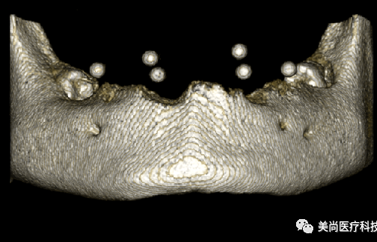

单独扫描放射导板过程

放射导板最终成像

准无牙颌传统数字化设计生产流程:

数据准备流程-CBCT数据

数据准备流程-模型数据(口外模型扫描仪光学扫描、口内扫描仪直接扫描)